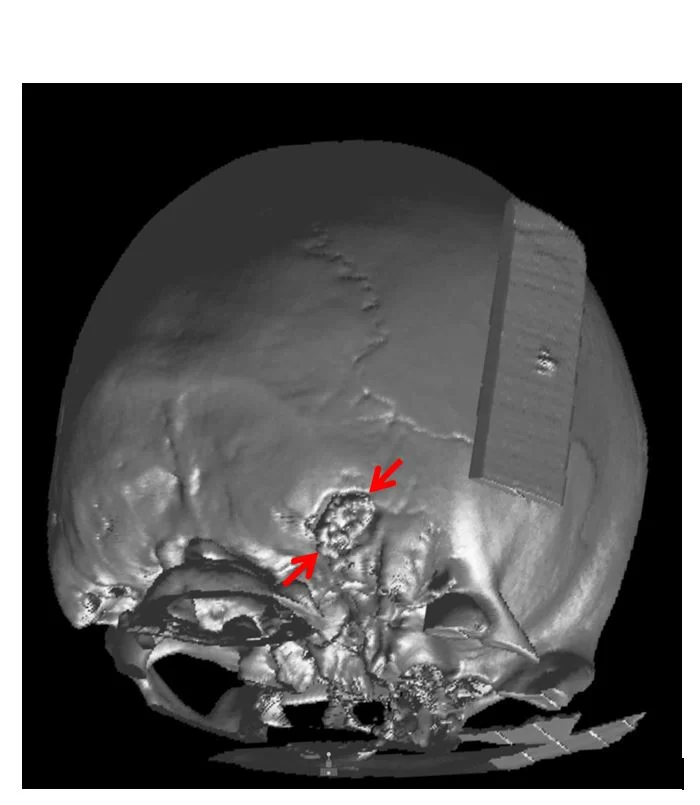

Μίνι οπισθομαστοειδική κρανιοτομία

Η μίνι οπισθομαστοειδική κρανιοτομία χρησιμοποιεί ένα μικρό άνοιγμα στο οστό πίσω από το αυτί (Εικόνα 3) για να προσπελάσει ακουστικά νευρινώματα, μηνιγγιώματα, επιδερμοειδείς όγκους και όγκους της παρεγκεφαλίδας όπως αιμαγγειοβλαστώματα και μεταστατικούς όγκους.

Είναι επίσης η κύρια προσέγγιση για μικροαγγειακή αποσυμπίεση των κρανιακών νεύρων (για νευραλγία τριδύμου ή για σπασμό του ημιπροσώπου). Συχνά συνδυάζεται με τη χρήση του ενδοσκοπίου (Εικόνα 4).